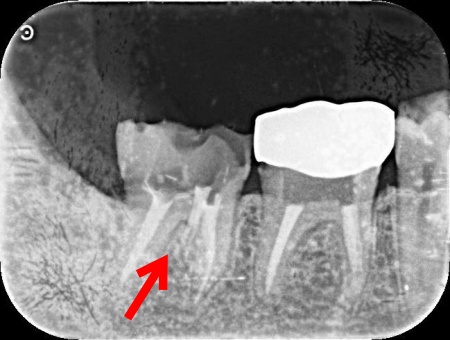

| 診断 | 拝見したところ、右下奥歯は神経や血管が通る根管の清掃・消毒を行う根管治療の途中でした。 レントゲン撮影をして確認した結果、本来処置が必要な根管ではない部分が削られ、歯に通常は存在しない穴があく「パーフォレーション(穿孔)」の状態であることが判明しました。 そのため治療しなければならない根管には、まだ適切な処置が行われていない状況です。 このまま治療されていない根管やパーフォレーション部分を放置すると、細菌感染の温床となり痛みだけでなく顎の骨にまで影響を及ぼし、最終的には抜歯が必要となる可能性があります。 以上のことから、早急な治療が必要と診断しました。 |